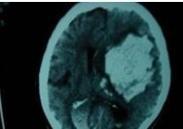

迟发性外伤性脑内血肿

628健康网为您分享有关迟发性外伤性脑内血肿的症状,迟发性外伤性脑内血肿的治疗方法,迟发性外伤性脑内血肿的预防知识...

急性硬脑膜下血肿

628健康网为您分享有关急性硬脑膜下血肿的症状,急性硬脑膜下血肿的治疗方法,急性硬脑膜下血肿的预防知识,急性硬脑膜下血...

高血压性脑出血

628健康网为您分享有关高血压性脑出血的症状,高血压性脑出血的治疗方法,高血压性脑出血的预防知识,高血压性脑出血的症状...

急性脑内血肿

628健康网为您分享有关急性脑内血肿的症状,急性脑内血肿的治疗方法,急性脑内血肿的预防知识,急性脑内血肿的症状图片,急...